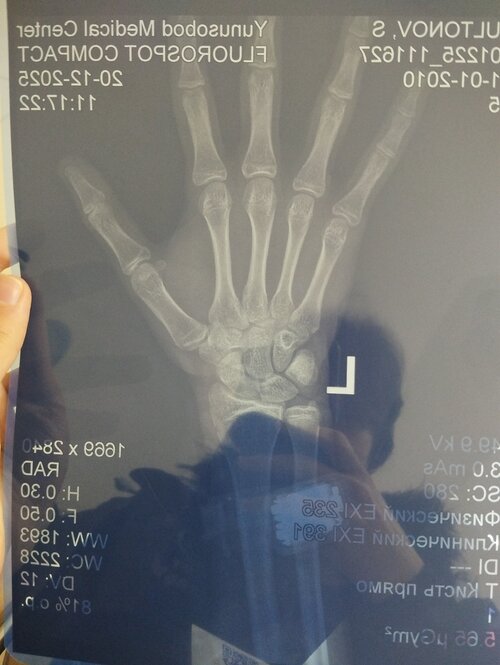

i did rengen and it said my growth plates are slightly opened, and my skeleton age is 16 yo. i am 173 cm, same as my dad an mom is 160, whats my final height?

It looks like the growth plates are barely open.

Phalanges & Metacarpals growth plates appear to be mostly closed. your growth plate for the radius is beginning to fuse, the ulna is Also showing advanced mineralization. I would guess your making it to about 175-176 by the time your 18.